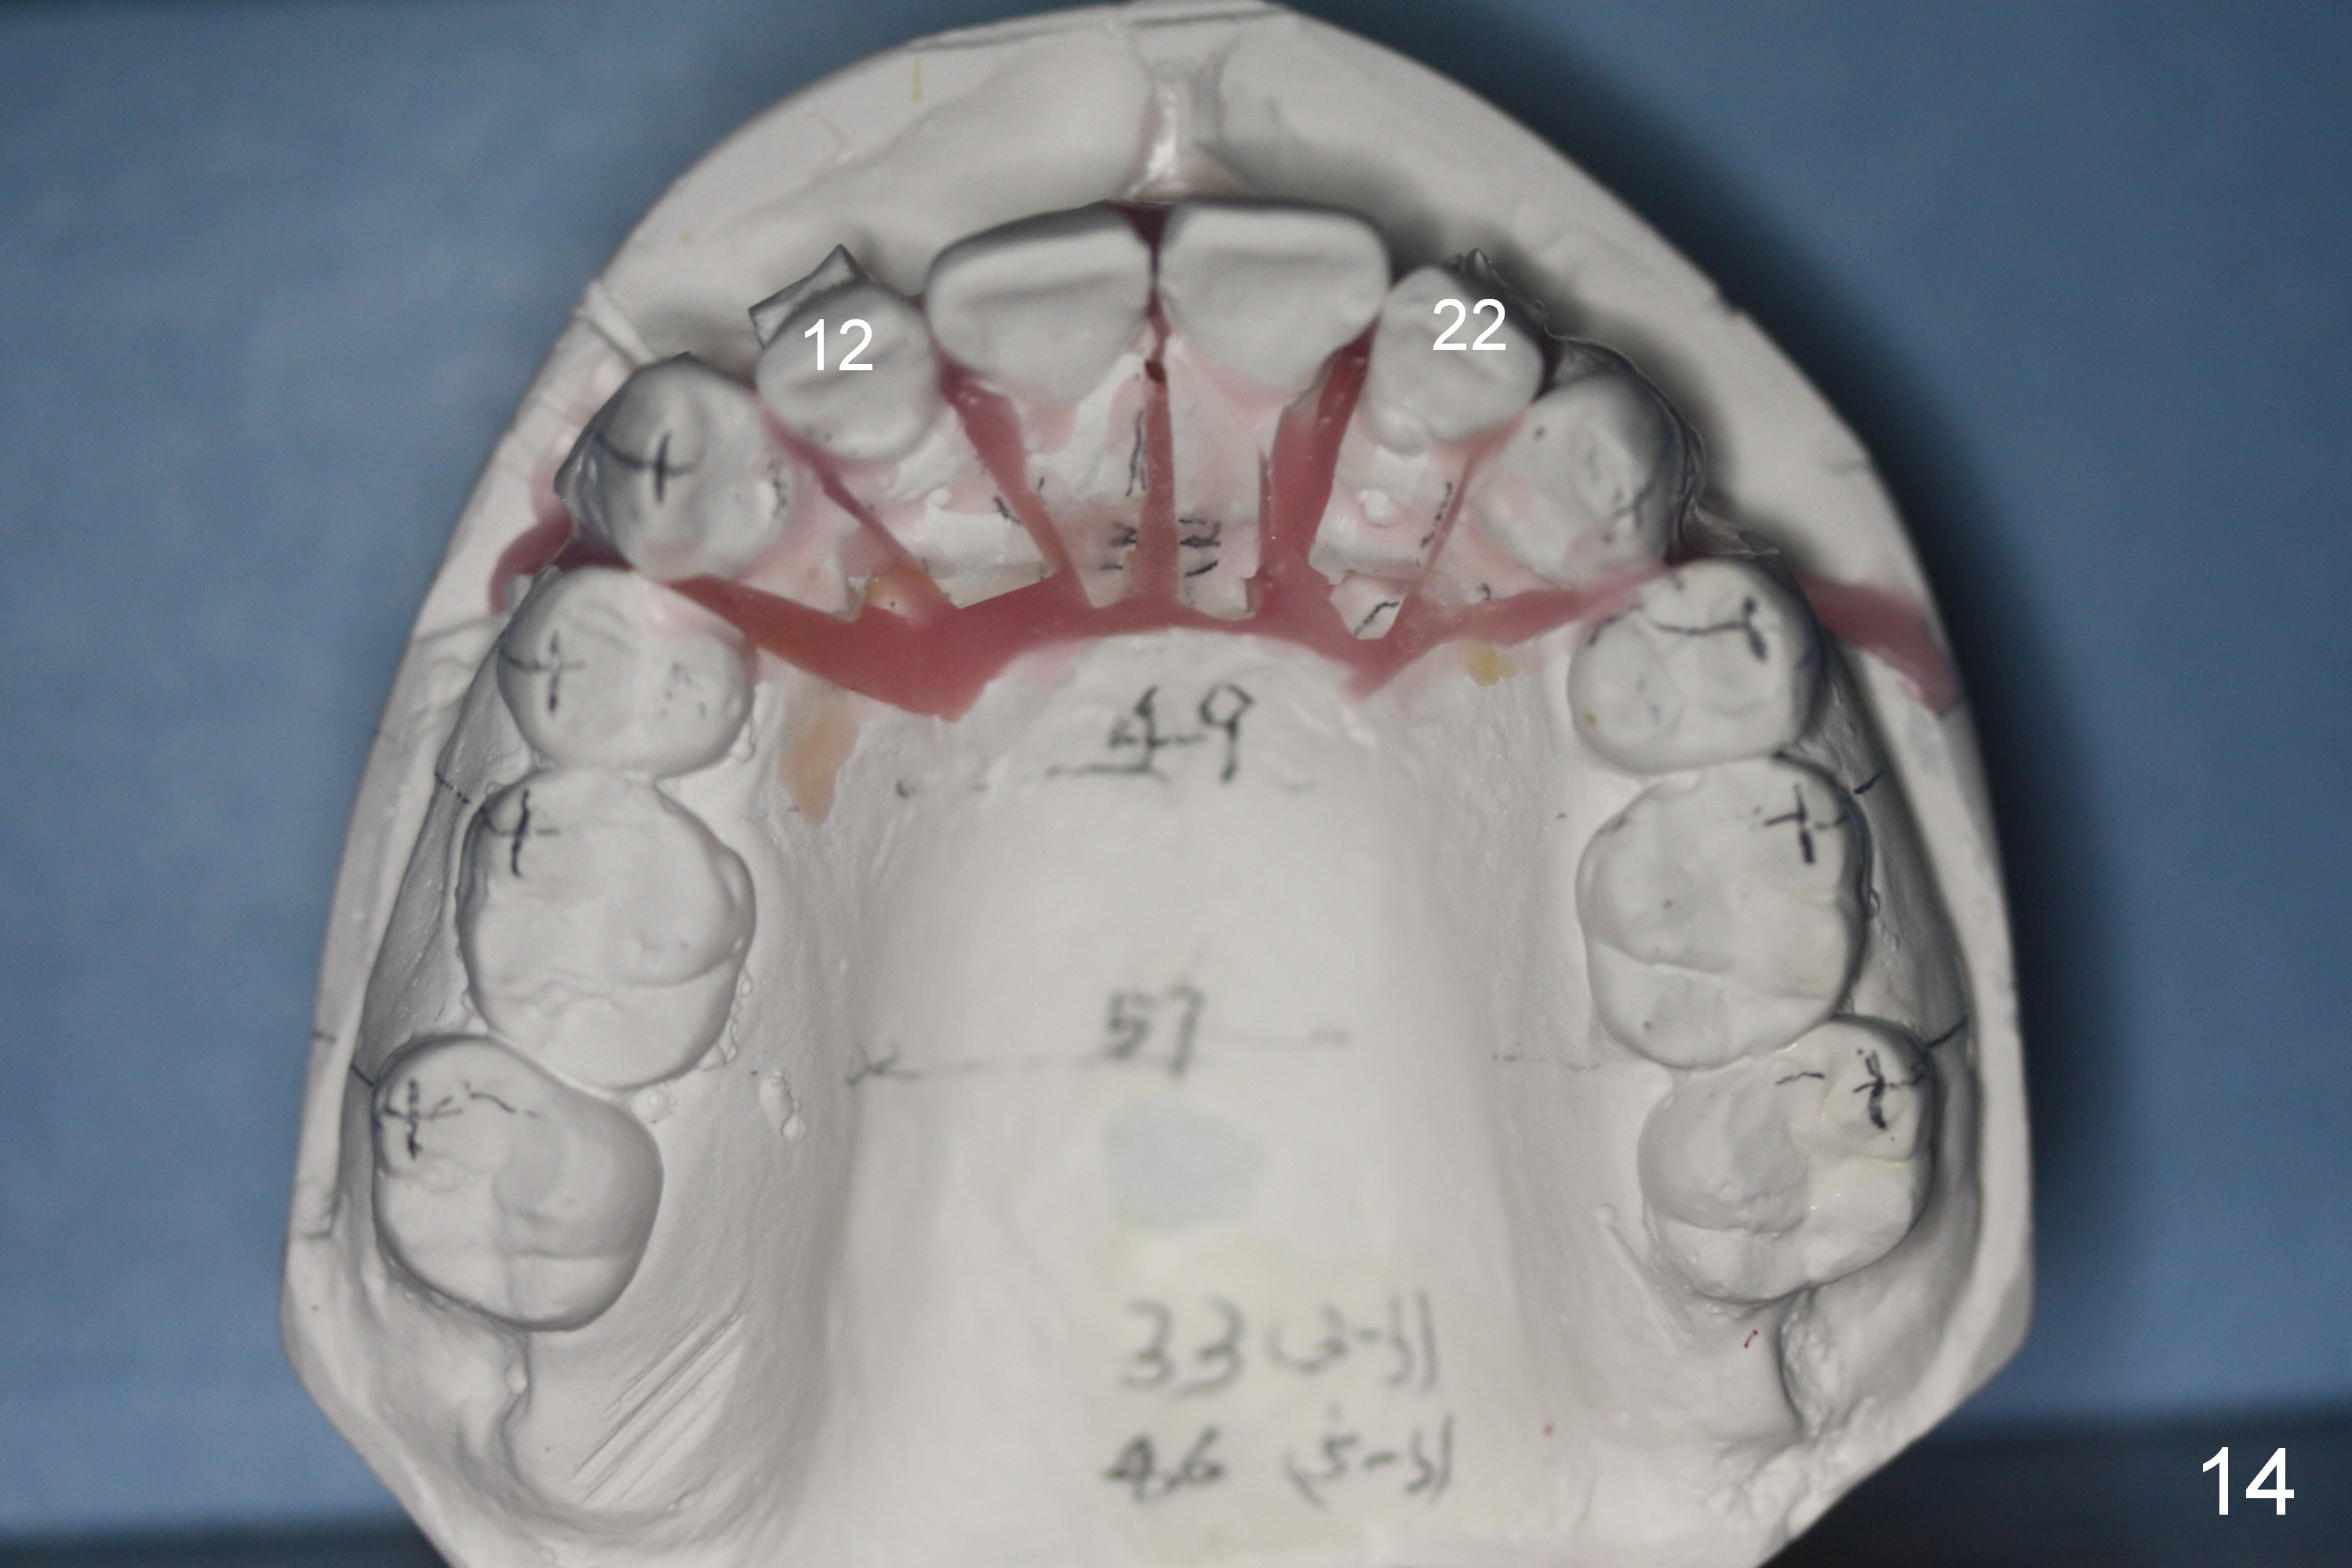

A 37-year-old man requests orthodontic treatment for severe crowding with 3 blocked-out incisors (Fig.1-5: 12,22,31 (International numbering, pronounced one two, two two and three one)). The upper and lower arches are pointed (Fig.4,5). The best option is extraction of 4 bicuspids (Fig.11-15).

His profile is convex with lip strain. After alignment of the anterior teeth, check the facial profile to determine whether it is necessary to distalize the anterior teeth or not. If it is, the distalization will be done with the aid of an implant at 47 (Fig.1,5 (residual roots)) and 3 mini-implants at the 3 other quadrants. An extra mini-implant will be placed at the upper right quadrant to intrude 17 (Fig.1 arrow).

There may be limited space for placement of these blocked out incisors. Do not have to place them at the time of bracketing until space has been created by arch wire sequence and open coil spring. It would be ideal to use labial torque brackets or place brackets upside down (Jenny's idea). In fact, the patient finishes ortho treatment in an orthodontist's office without intrusion of 17. Magicore will be placed at 47 to intrude 17 or simply for restoration.